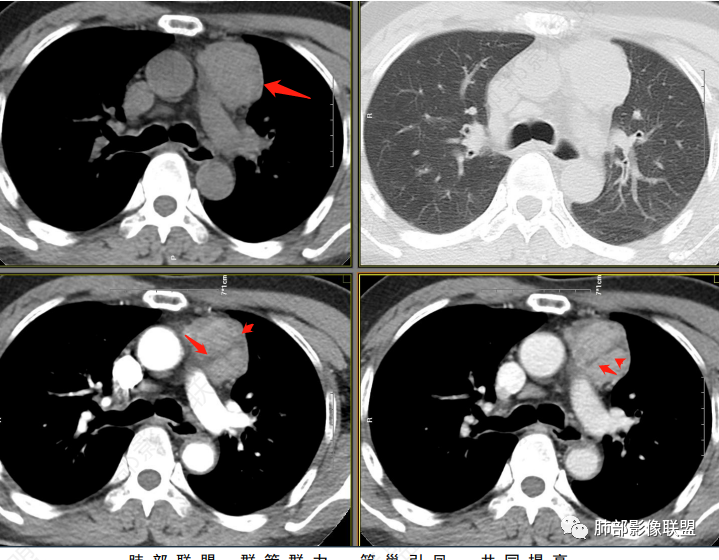

一、赵国干:联盟晨读病例:中年男性,左前纵隔团块状占位,增强呈持续渐进性强化,常规首先考虑胸腺瘤,其次CD、血管瘤(静脉瘤)及副节瘤

三、谢加平:中老年男性,前纵隔偏左侧肿块,类圆形,无分叶,左侧内乳动脉供血增粗,实性内不均匀强化(具体CT值),有低强化分隔区,肿块内侧边缘毛糙,提示有侵犯特点。有乏力(肌无力)表现,位置来源胸腺瘤(AB?B3型?),与胸腺神经内分泌ca和转移鉴别,Nse抗原、角蛋白19片段和CEA,有不明原因腹痛,可结合腹部CT平扫及增强,排除腹腔内原发肿瘤病变

四、吕军浩:男,56,腹痛、乏力一月,虽然说胸腺瘤可有肌无力变现,纵隔是否责任病灶,难说。就看术后症状能不能改善。影像特点:1、 血管前间隙胸腺区占位,偏一侧,未过中线,在胸腺瘤是良性表现 ;2 、轮廓大致清晰,增强后似见病灶周围渗出样模糊,可能系占位效应,血管淋巴回流受阻引起 ;3 、多个小灶坏死(可以鉴别CD,前无神,所以神经源性肿瘤的AB区不用不用考虑),有低强化分隔;4、 与周围血管间隙还是非常清楚的;5 中度流入型强化 , 综合大概率拍死 AB型胸腺瘤

五、王建国:左前纵隔软组织密度肿块影,边界尚清,密度较均匀,增强扫描渐进性明显强化,其内可见斑片状及线条样低密度影,内乳动脉增粗,考虑胸腺瘤(AB型),鉴别神经内分泌肿瘤,典型类癌

六、白光宇:左前纵膈肿块,边缘光整,明显不均匀渐进强化,其内条片状低密度影,纵膈多发淋巴结,考虑胸腺瘤,胸腺类癌待排

七、冰柠雨露司桂英:前纵隔偏左软组织密度包块,密度较均匀,轮廓规整,与邻近血管结构分界尚清,纵隔未见异常增大淋巴结,增强后中等度强化,内可见低密度分隔,考虑胸腺瘤,AB型?

八、姜文强:晨读病例,中老年,慢性病史。前纵隔占位,纵隔侧和主动脉脂肪间隙清晰,內乳动脉向外推挤,胸膜掀起,轻度强化,内坏死,考虑胸腺瘤

九、宋明亮:男,56岁反复腹疼乏力一个月。前纵隔偏心占位性病变,边缘较清,无明显坏死囊变,似见纤维分隔。考虑胸腺瘤,AB型

十、钟学兰:中年男性,前纵隔偏侧占位,周围血管间隙可见,临床腹痛乏力,增强明显延迟强化,内见低密度纤维分隔,胸腺类癌与胸腺瘤AB型间鉴别